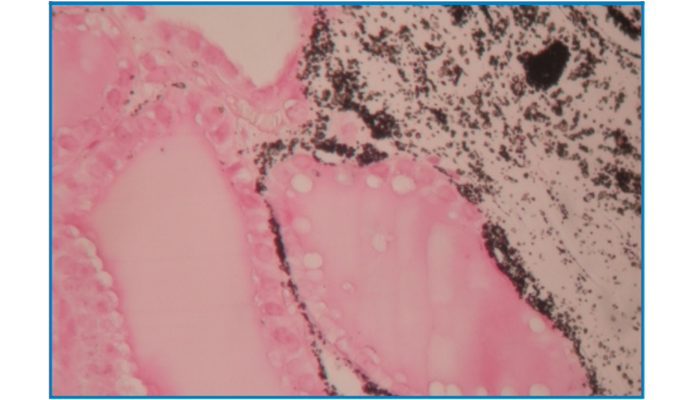

Calcium Salt Stain

(Sliver nitrate staining medthod)

Intended for the staining neutral fat.